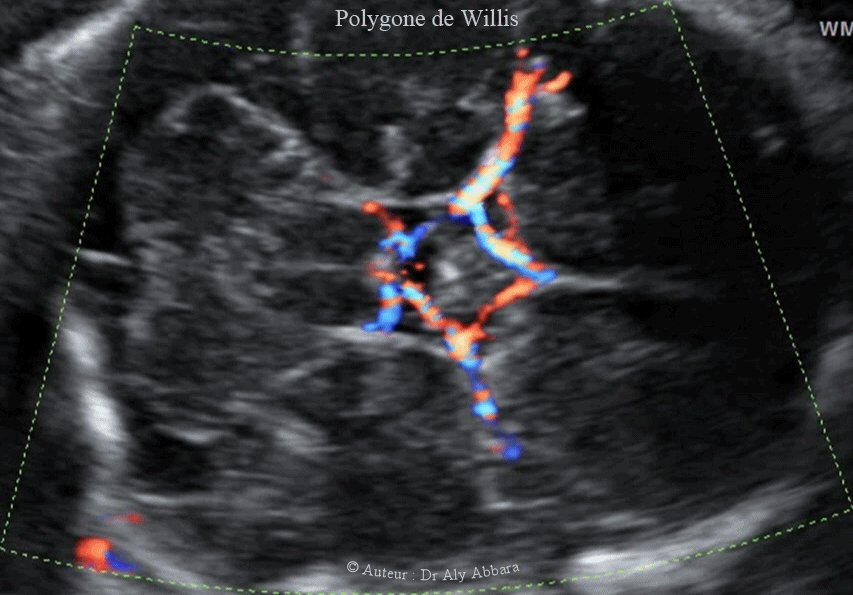

Image échographique animée montrant les éléments vasculaires artériels cérébraux composant

le polygone vasculaire de Willis :

* Artère cérébrale moyenne gauche (ACM-G)

* Artère cérébrale moyenne droite (ACM-D)

* Artère cérébrale postérieure gauche (ACP-G)

* Artère cérébrale postérieure droite (ACP-D)

* Artère cérébrale antérieure gauche (ACA-G)

* Artère cérébrale antérieure droite (ACA-D)

* Artère communicante postérieure gauche (A-COM-P-G)

* Artère communicante postérieure droite (A-COM-P-D)

* Artère communicante antérieure (A-COM-A)

Cerveau fœtal à 29 SA - coupe axiale passant par la base du cerveau..